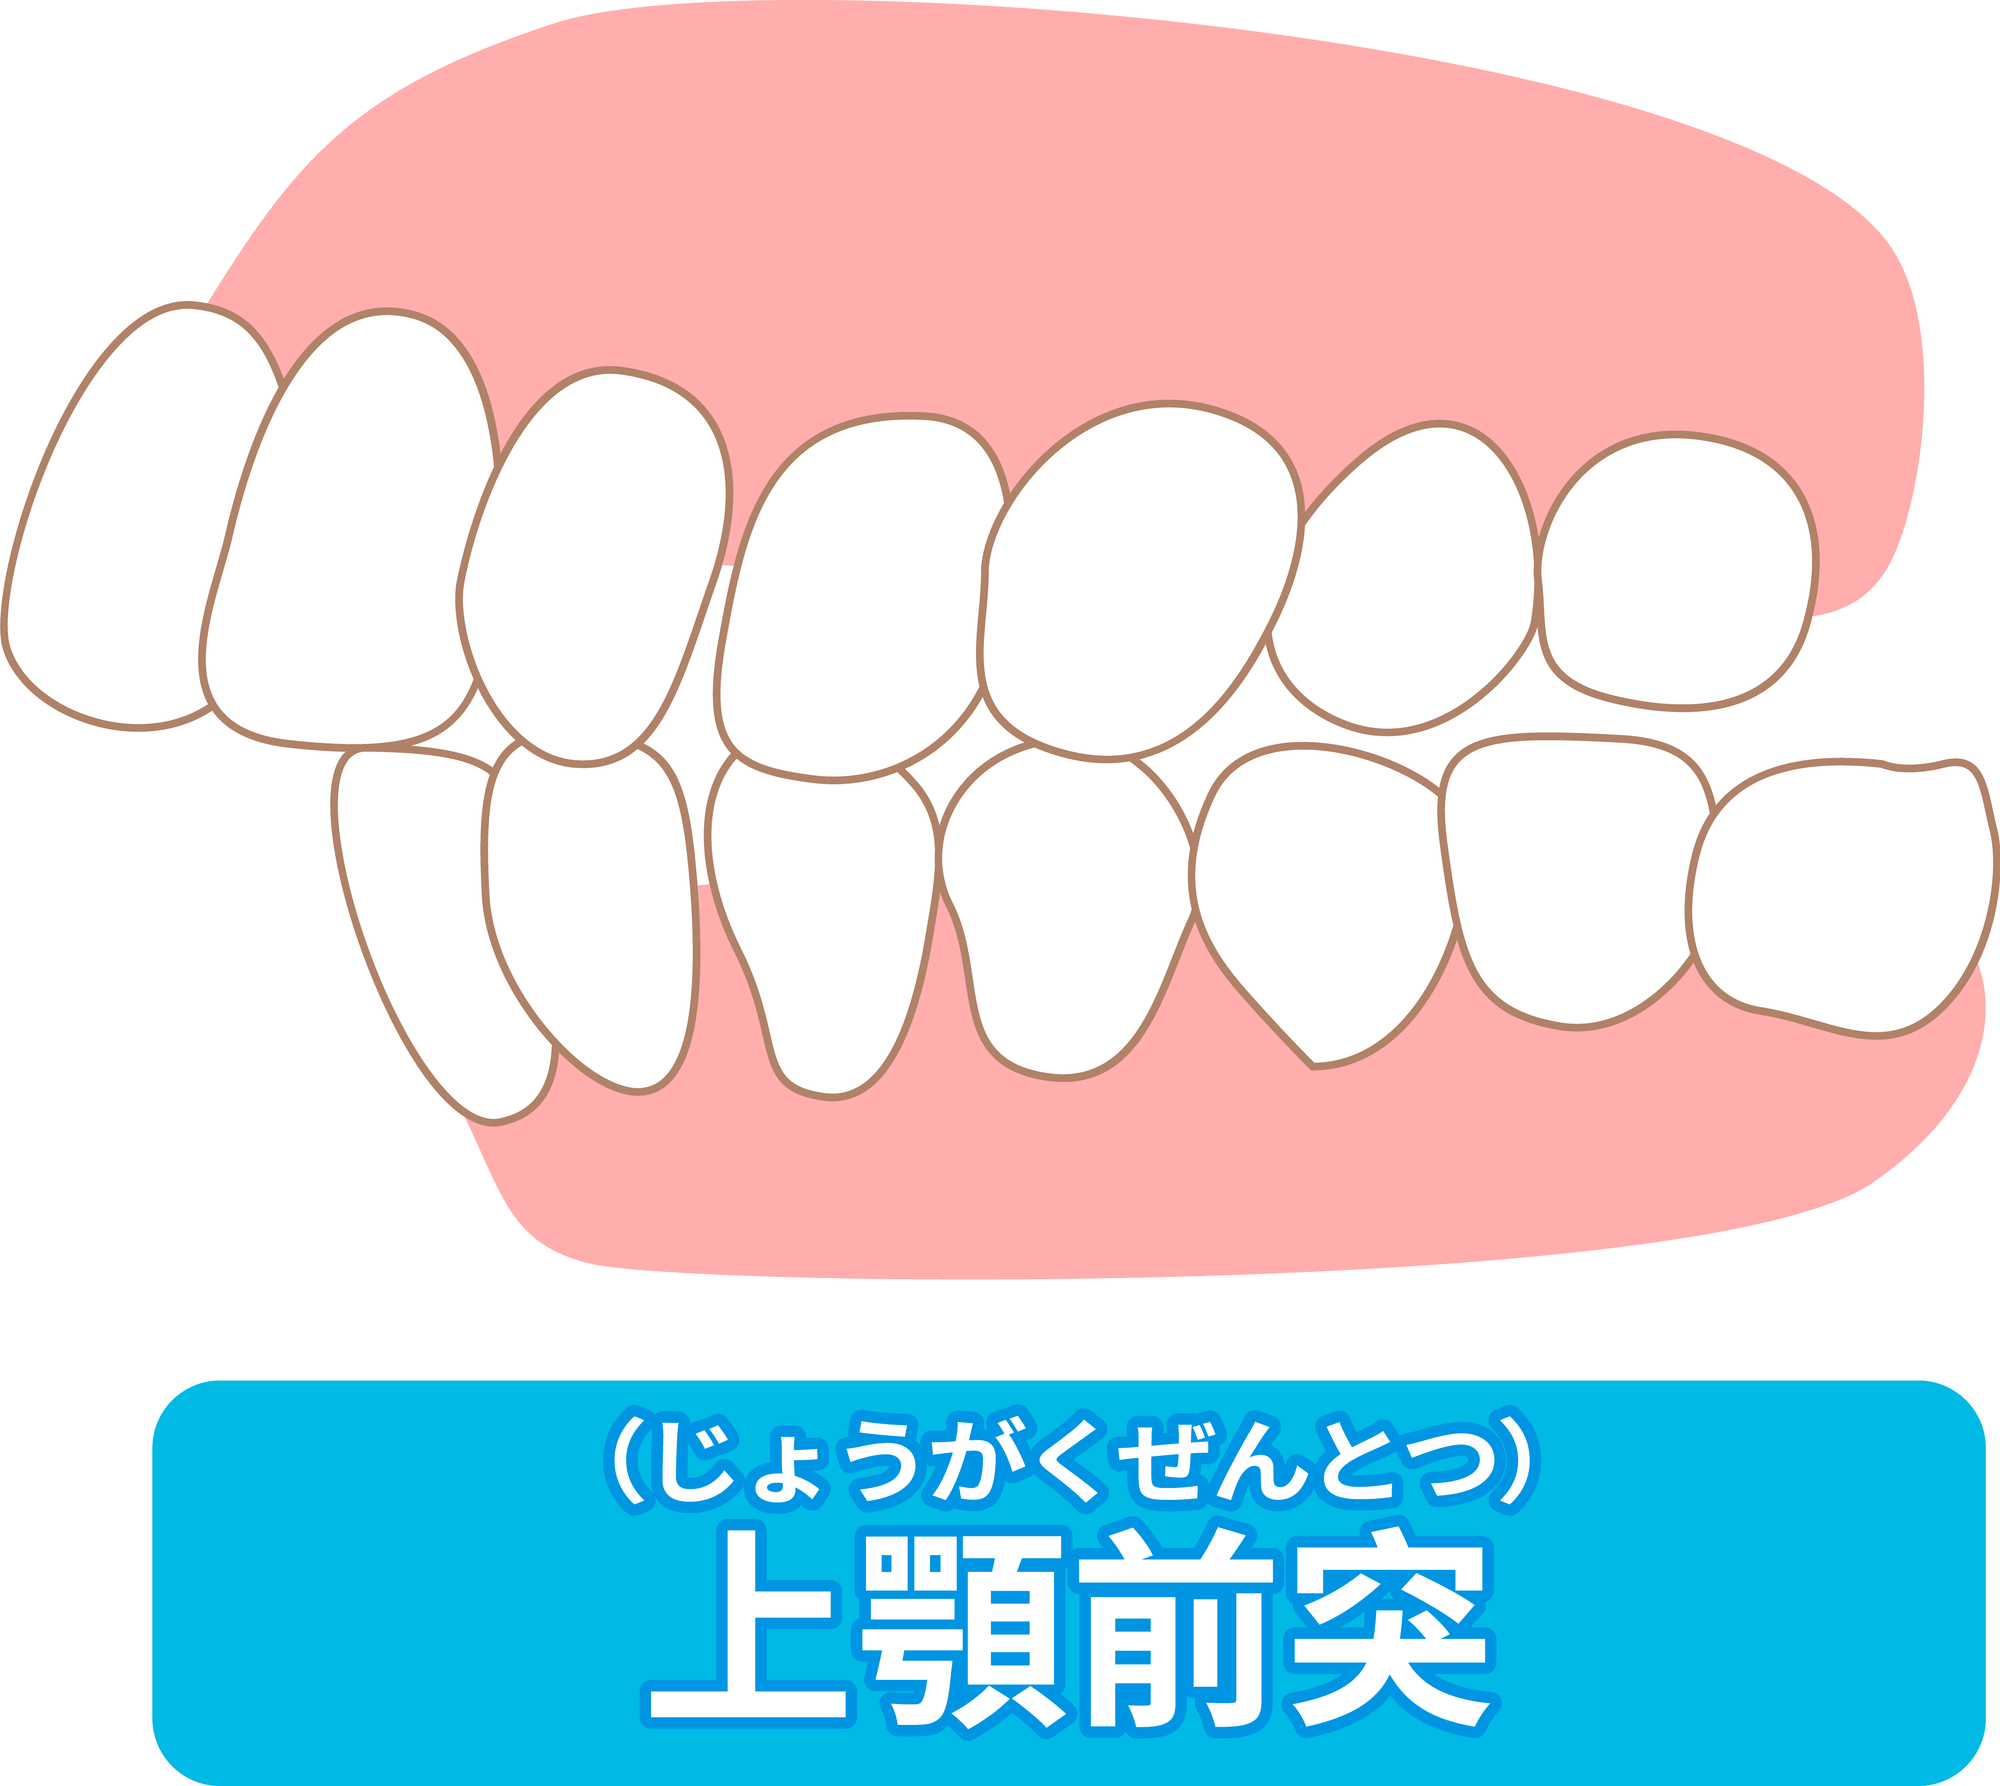

出っ歯だと喘息になる!?原因や関係性は・口呼吸について

【舌側矯正症例】前歯の凹凸・出っ歯(上顎前突)・口元を下げたい